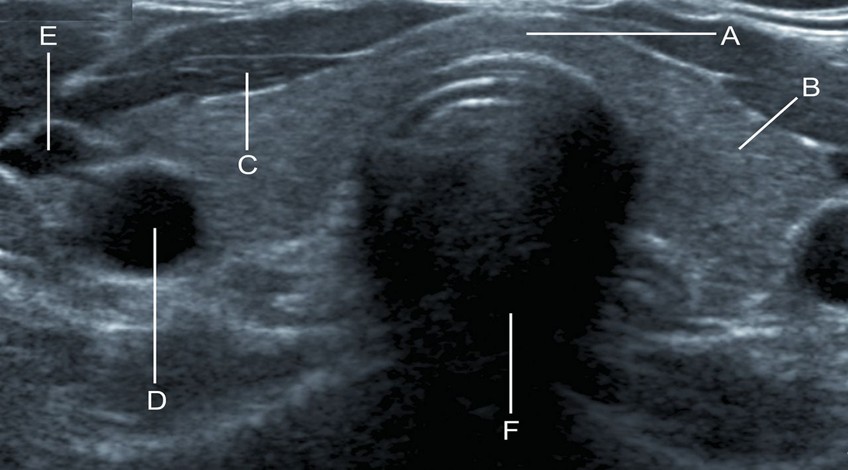

Ecotomografía Tiroidea

- ¿Qué es? Es un examen que estudia la glándula tiroides que se encuentra ubicada en la región anterior del cuello.